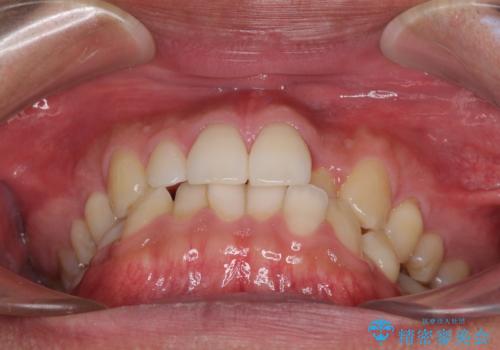

前歯のデコボコとクロスバイト インビザライン矯正治療

- 前歯のデコボコとクロスバイトを治したいとのことで来院された患者様です。

上下顎ともに歯列全体の側方拡大を行い、下顎前歯はIPR(歯と歯の間を削る)によってデコボコとクロスバイトが解消するように設計し、インビザラインにより治療を行うこととしました。

2年弱で終了する予定でしたが、途中来院されなかった時期があり、その後舌側転位している前歯を動かせるところまで動かしたいとのことで4年ほど治療を継続されました。